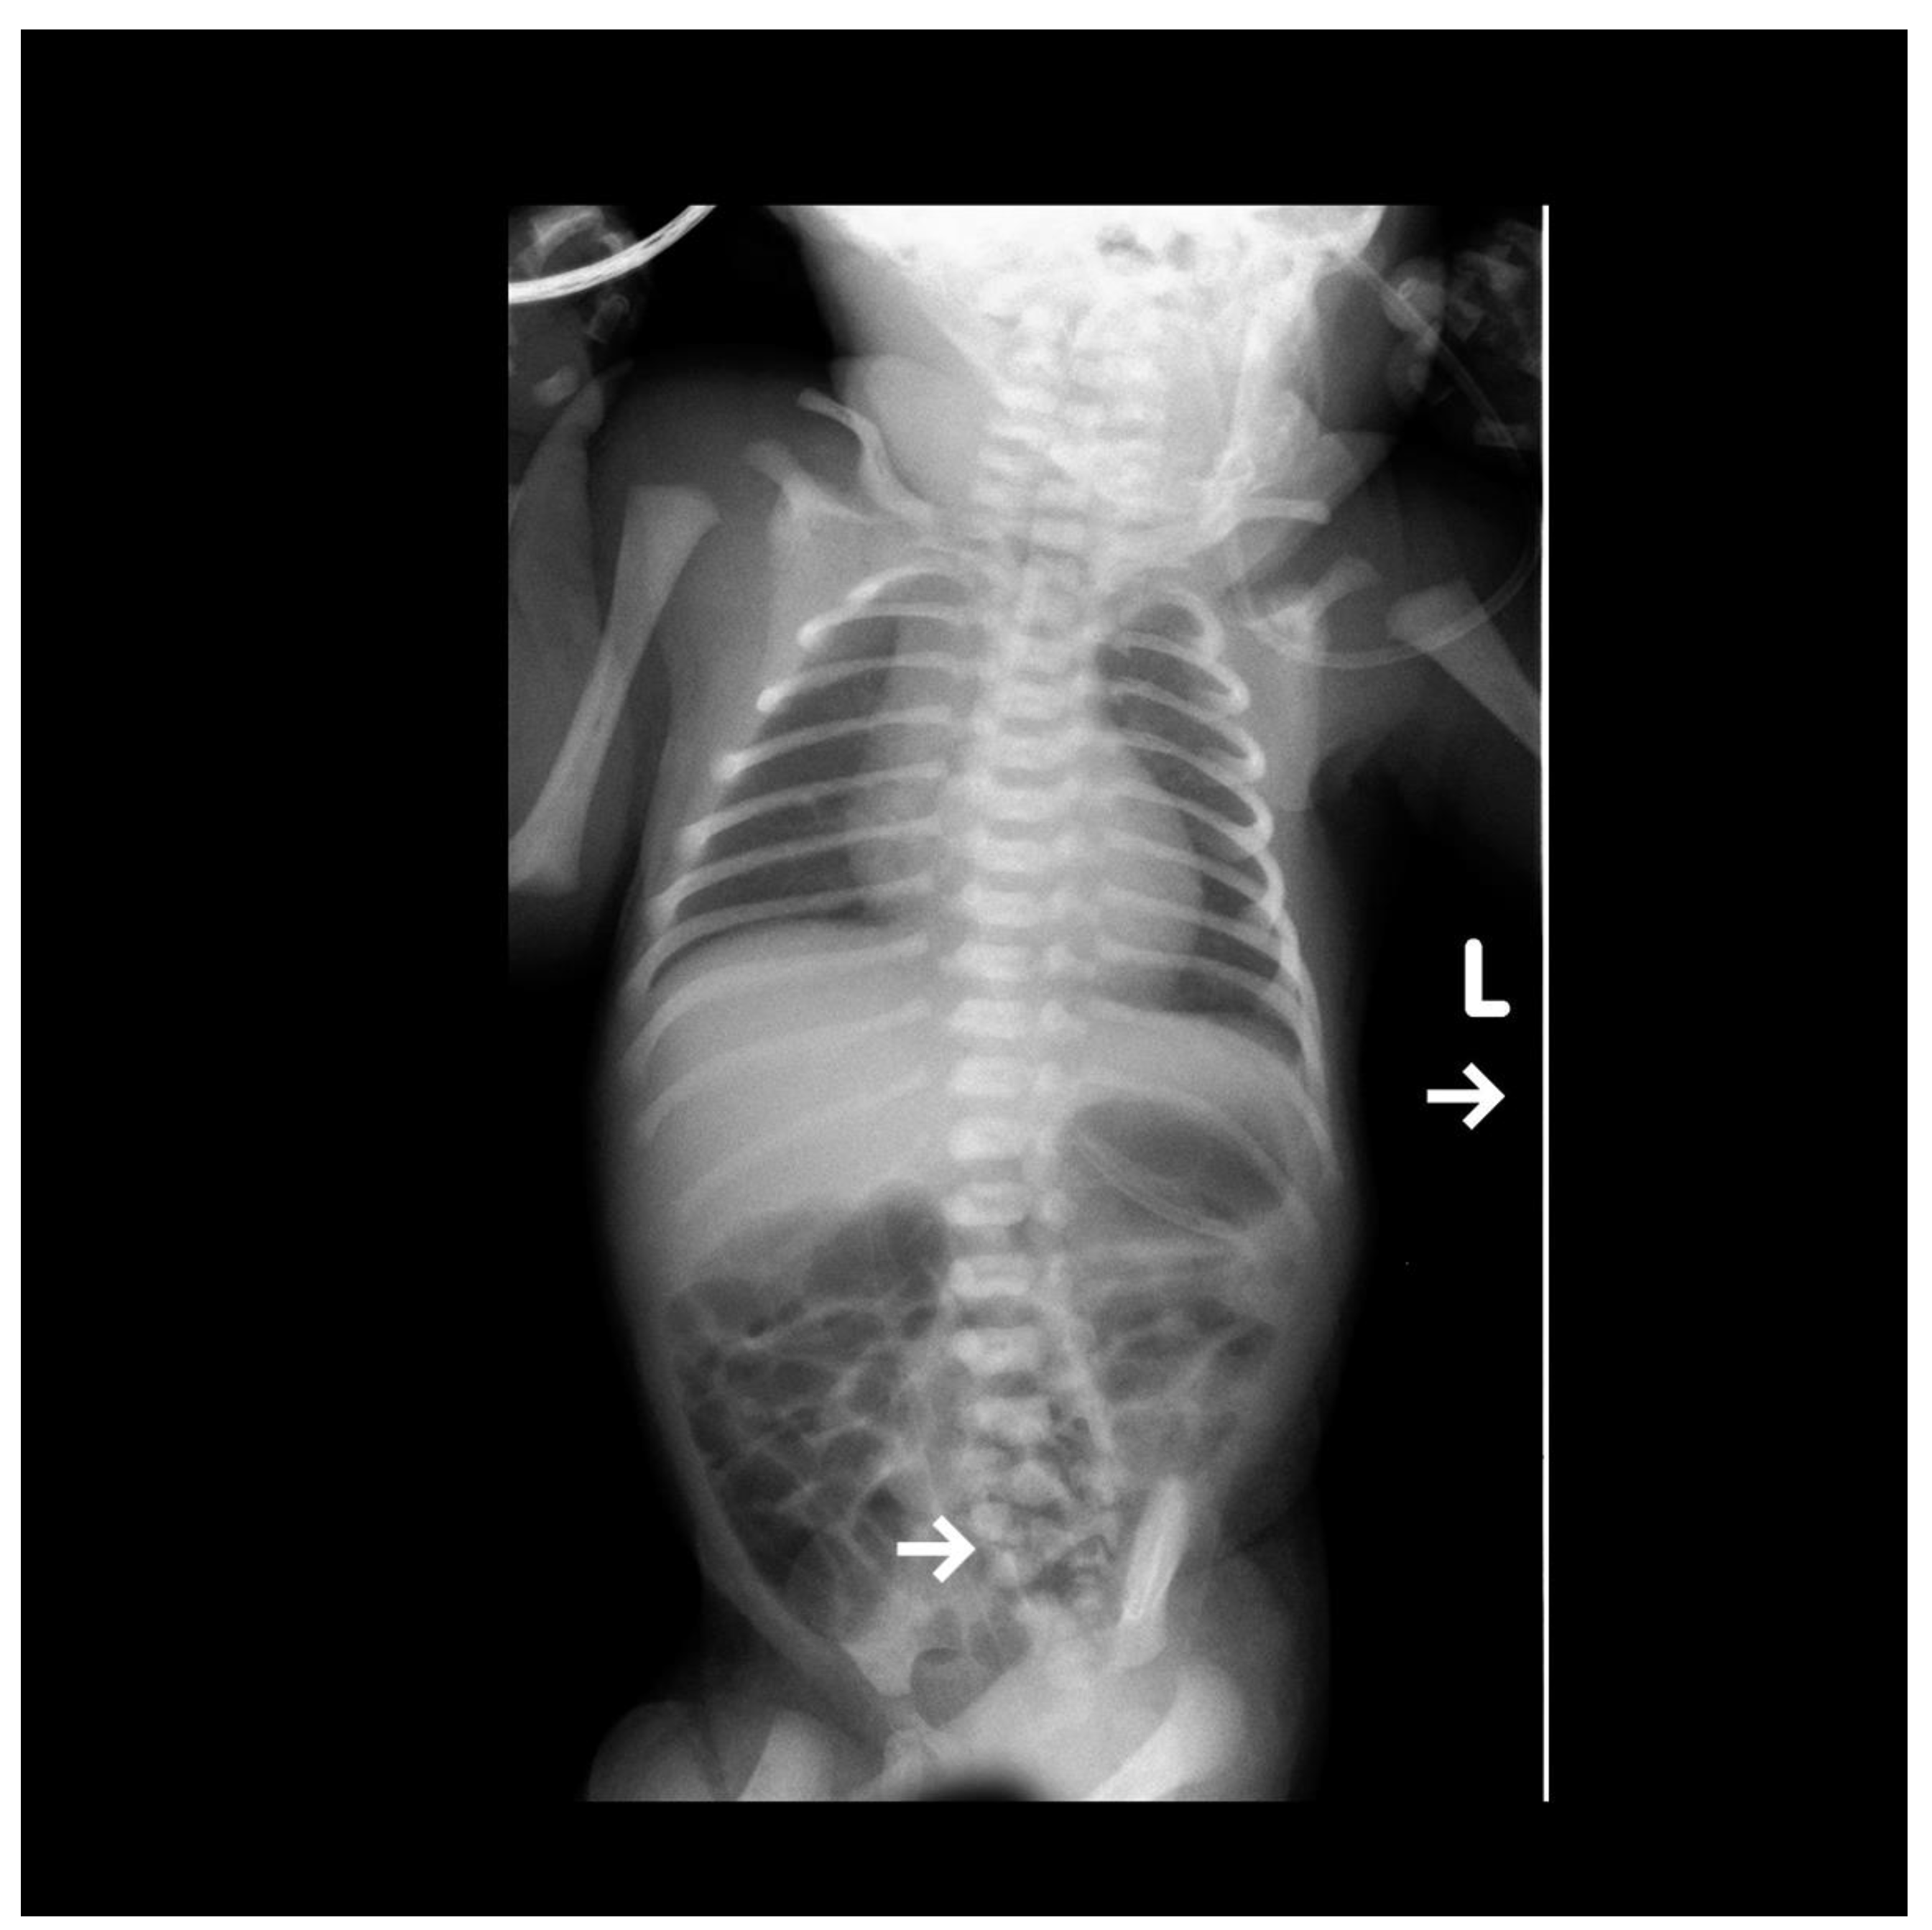

Congenital Anterior Dislocation of the Sacrococcygeal Bone in a Newborn

Fabijan, A.; Polis, B.; Zakrzewski, K.; Zawadzka-Fabijan, A.; Korabiewska-Pluta, S.; Nowosławska, E. Congenital Anterior Dislocation of the Sacrococcygeal Bone in a Newborn. Diagnostics 2023, 13, 2108. https://doi.org/10.3390/diagnostics13122108